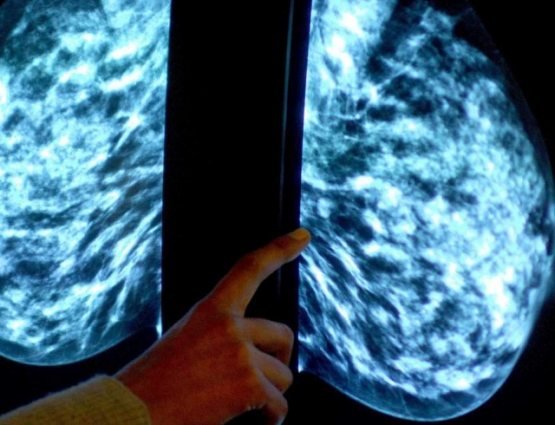

Кўкрак бези саратонидан ҳалок бўлаётганлар сони кўпайиб бормоқда

Кўкрак бези саратони билан боғлиқ ўлимлар 1989 йилдан буён давом этмоқда ва бугунги кунда ушбу касаллик туфайли ҳар йили 11,5 минг киши ҳаётдан кўз юммоқда, деярли 55 мингга яқин аёлга яна шундай ташхис қўйилган.

Англиянинг Миллий соғлиқни сақлаш хизматининг 2018 йил июнь ойида берган маълумотларига кўра, ҳар 100 минг кишидан 48 таси кўкрак бези саратонидан ҳалок бўлган.